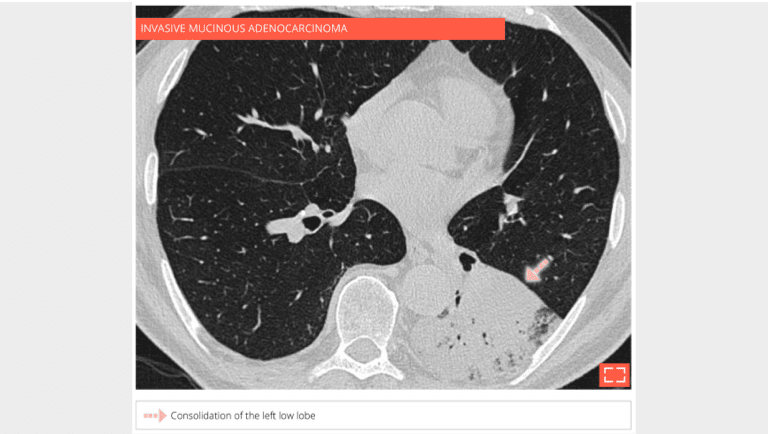

• pneumonic-type mucinous adenocarcinoma

3. Alveolar consolidation